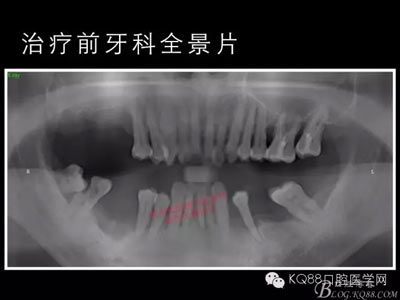

下面的種植病例是為患者提供全口牙齒治療修復完整過程的下頜部分,我們門診和患者共同配合下目前取得了較好的修復效果,即將開始的上頜牙齒治療修復過程仍然艱辛。